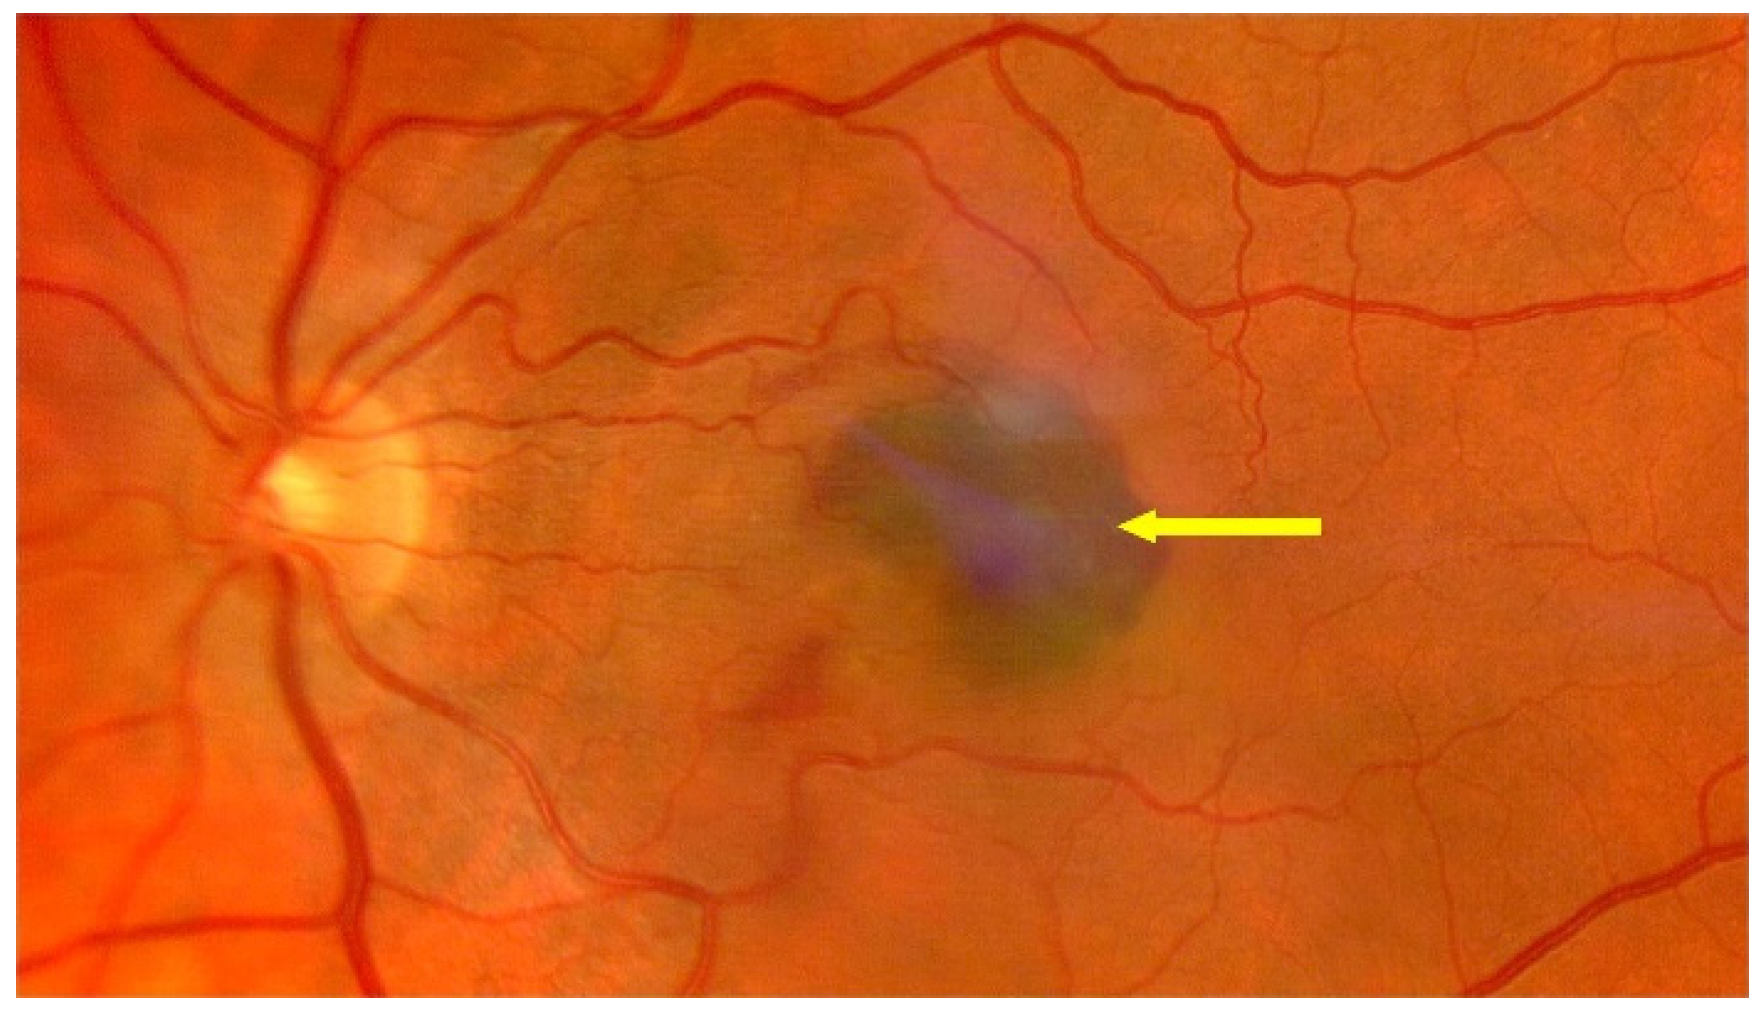

3. Treatment of Neovascular AMD

3.2. Anti-VEGF Drugs

3.2.1. General Information

3.2.2. Anti-VEGF Therapies